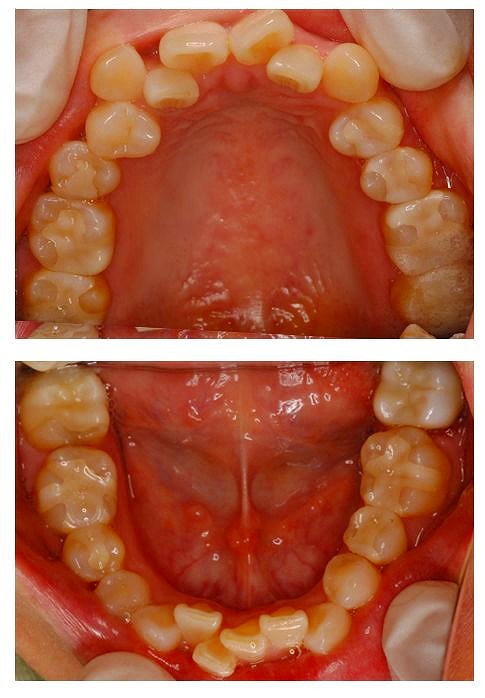

口の中を見ると、所々しか金属がはいってないようにみえます。

しかし、今回は症状もひどく、精神的にも悩まれた期間が長いようで、すべてセラミックのものと交換しました。

もちろん、セラミックですからアレルギーはありません。というわけで、お口の中から金属が消えて、心も晴れて歯も白くなりました。